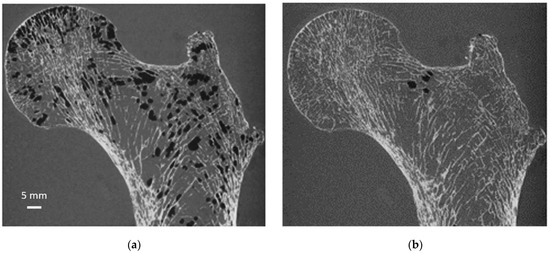

As illustrated in Figure 6, air bubbles were clearly visible as darker pixels in the μCT images. The corresponding air volume present inside S1 was 12.4 cm3 (Table 1). During the vacuum procedure, the movement of air bubbles from the bottom cross-section was clearly visible. Three vacuum cycles were applied, and the total amount of air bubbles still present in the bone microstructure was greatly reduced (<0.5%) of the total bone marrow volume (Table 1). Moreover, the residual amount of air bubbles after each vacuum cycle was evaluated in the case of S1. The results showed that the first vacuum cycle led to a significantly large reduction (98.8%) in air volume, while the remaining air volume was completely removed after two additional cycles (Figure 6 and Table 1).

Figure 6. Same coronal µCT plane before and after sample preparation. Same S1 µCT coronal plane before (a) and after (b) the application of our sample preparation technique and acquired at 0.051 mm isovolumetric resolution.